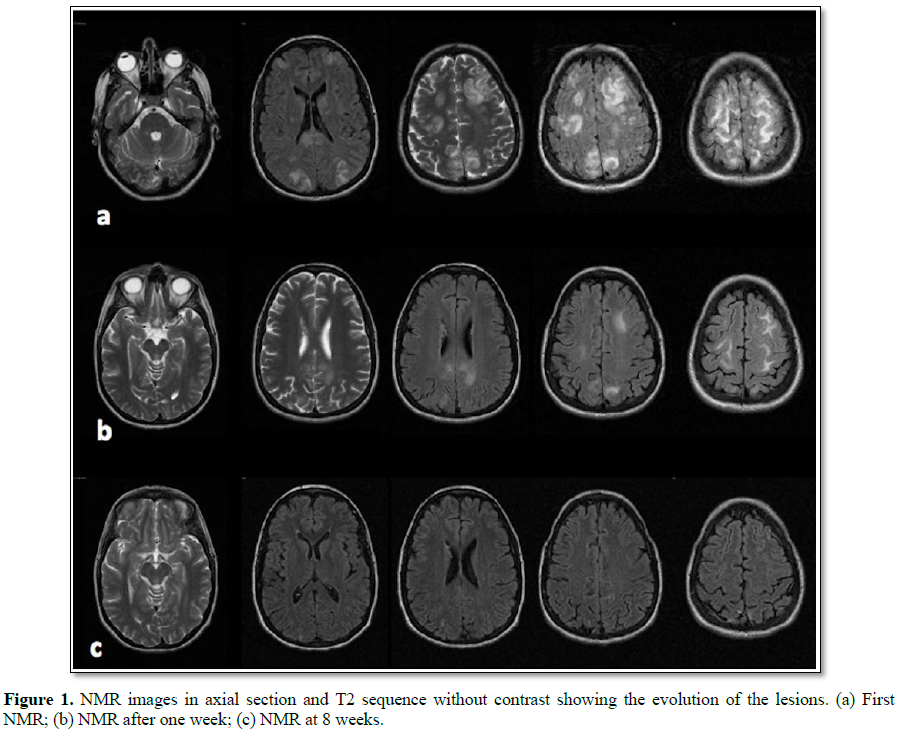

The patient is transferred to Intensive Care Unit for neurological and blood pressure monitoring. The study is completed with MRI and angiography MR, which allows discarding of aneurysmal lesions and shows a slight cerebral vasoconstriction component, being this findings compatible with PRES and with reversible cerebral vasoconstriction syndrome (RCVS) (Figures 1 and 2).

During her stay in ICU no seizures occurred, blood pressure is controlled using several intravenous treatments (labetalol, hydralazine and captopril) resulting in cessation of cephalalgia and visual alterations within the following 72 h. A week after admission, a control MRI is carried out, being the results consistent with PRES resolution stage.

The patient is discharged with antihypertensive as well as antidepressant treatments. The control MRI carried out a month later shows signs of regression of most of the alterations present in previous investigations, with only residual changes remaining.

Currently, the patient is in complete remission of the lesions as per MRI investigation and blood pressure of 106/70 mm Hg without further treatment as per hypertension clinic monitoring.

Appropriate imaging technique that supports the PRES diagnosis is the T2 weighted MRI images, showing images compatible with bilateral, symmetrical, vasogenic edema, localized, 98% of the cases, in the subcortical white matter in parietal and occipital lobes. In specific cases, localized lesions may appear in the upper frontal area, temporal lobes, cerebellum, brainstem and basal ganglia which require a more exhaustive differential diagnosis. Sequences of T1 MRI imaging or the use of CT scan images could help to rule out other lesions (tumors, encephalitis, subarachnoid hemorrhage, venous thrombosis, etc.).

MRI observed Lesions, in our case, are hyper intense, symmetrical, parietal-occipital, compromising mainly white matter consistent with vasogenic edema and confirming PRES diagnosis. Diffusion weighted images ruled out presence of cytotoxic edema.